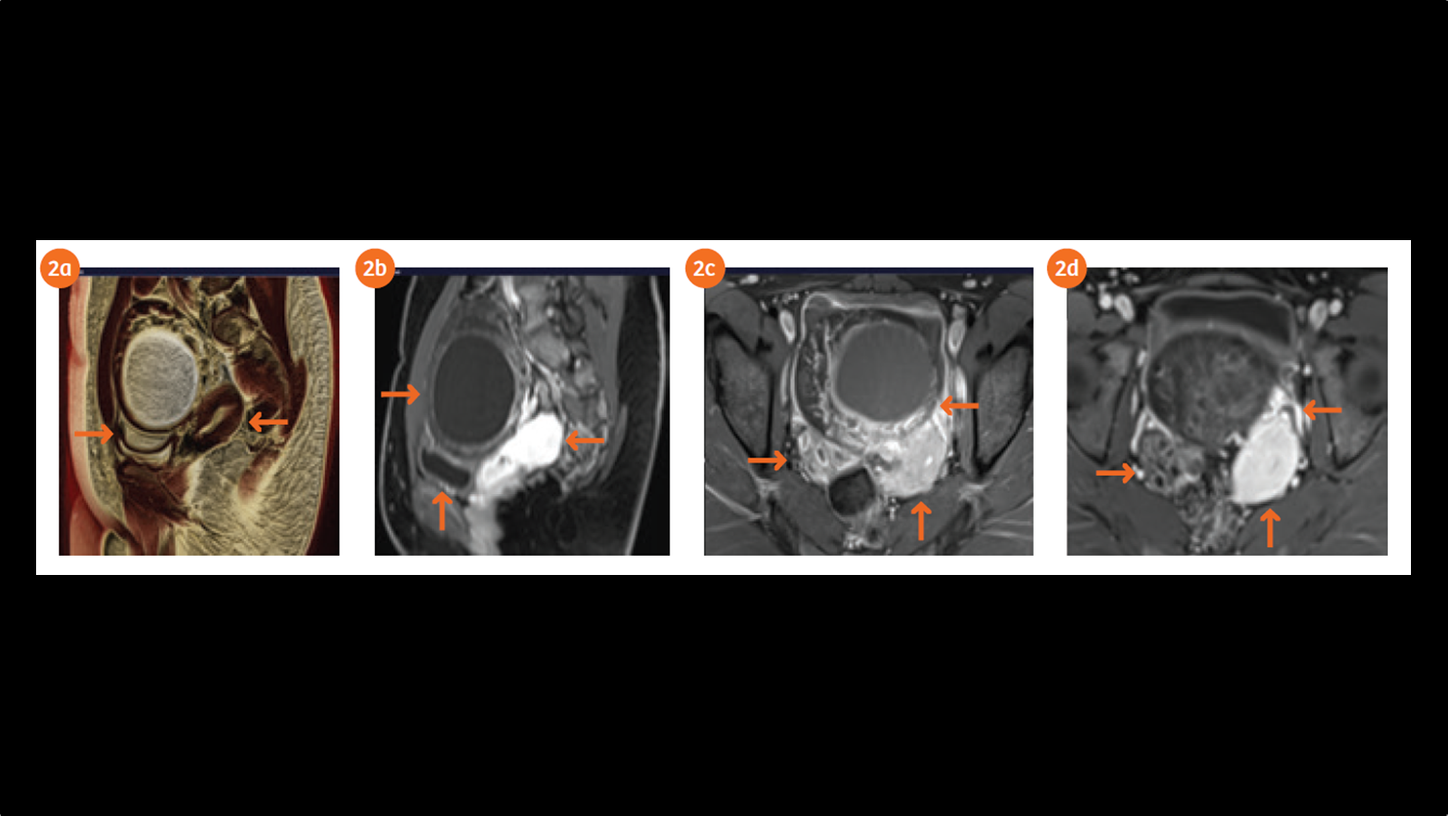

The pelvic ultrasound showed significant enlargement of the left ovary exhibiting a large anechoic cyst with edema of the ovarian stroma and free intraperitoneal fluid effusion. The color Doppler showed persistent arterial vascularity in the left ovary. The US appearance of the ovary raised high suspicion of left ovarian torsion. The pelvic MR exam performed on MAGNETOM Skyra 3T system demonstrates a large rounded hemorrhagic cyst within the left ovary measuring 70 x 70 mm in diameter with regularly thickened wall causing compression of the urinary bladder and displacing posteriorly the uterine body. The high tissue characterization MRI revealed edema and multiple foci of hemorrhage in the left ovarian stroma with twisting of the vascular pedicle in the left adnexa. Patient underwent surgical procedure and that lead to the torsion correction and cyst removal. After three months in the follow up ultrasound evidence, both the ovaries and the uterus were normal.